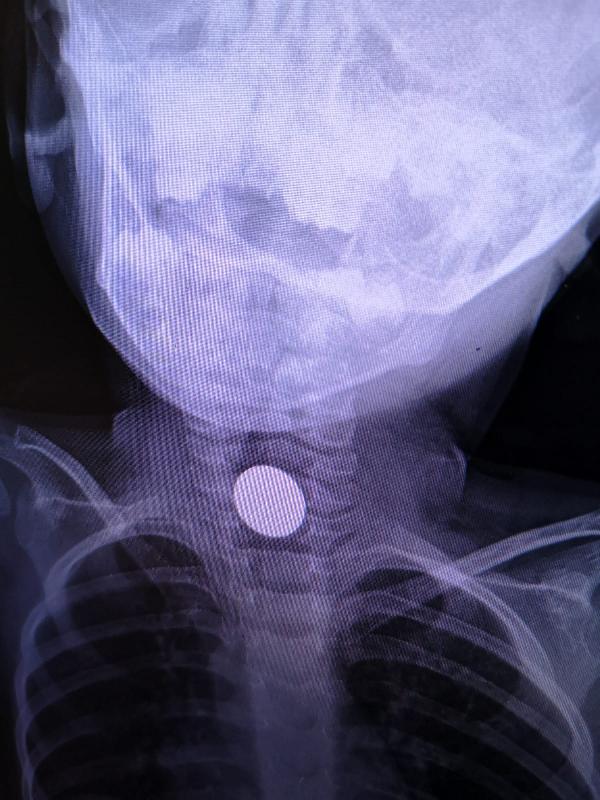

Madeni para, küçük çocuğun boğazına takıldı. Çocuk, ailesi tarafından İnegöl Devlet Hastanesi'ne götürüldü.

Burada yapılan ilk müdahalenin ardından küçük çocuk Bursa Şehir Hastanesi'ne sevk edildi. Madeni para, burada yapılan operasyon ile çıkartılırken, Yunus Emre Kaya'nın sağlık durumunun iyi olduğu öğrenildi.